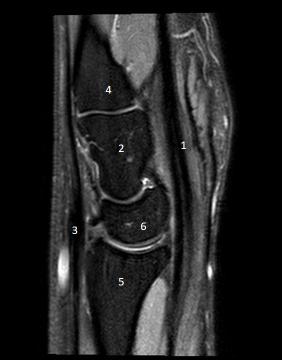

5 / 10

5. Observe a imagem acima. Que estrutura o número 5 se refere?

8 / 10

8. Observe esta imagem. Que estrutura corresponde ao número 2?